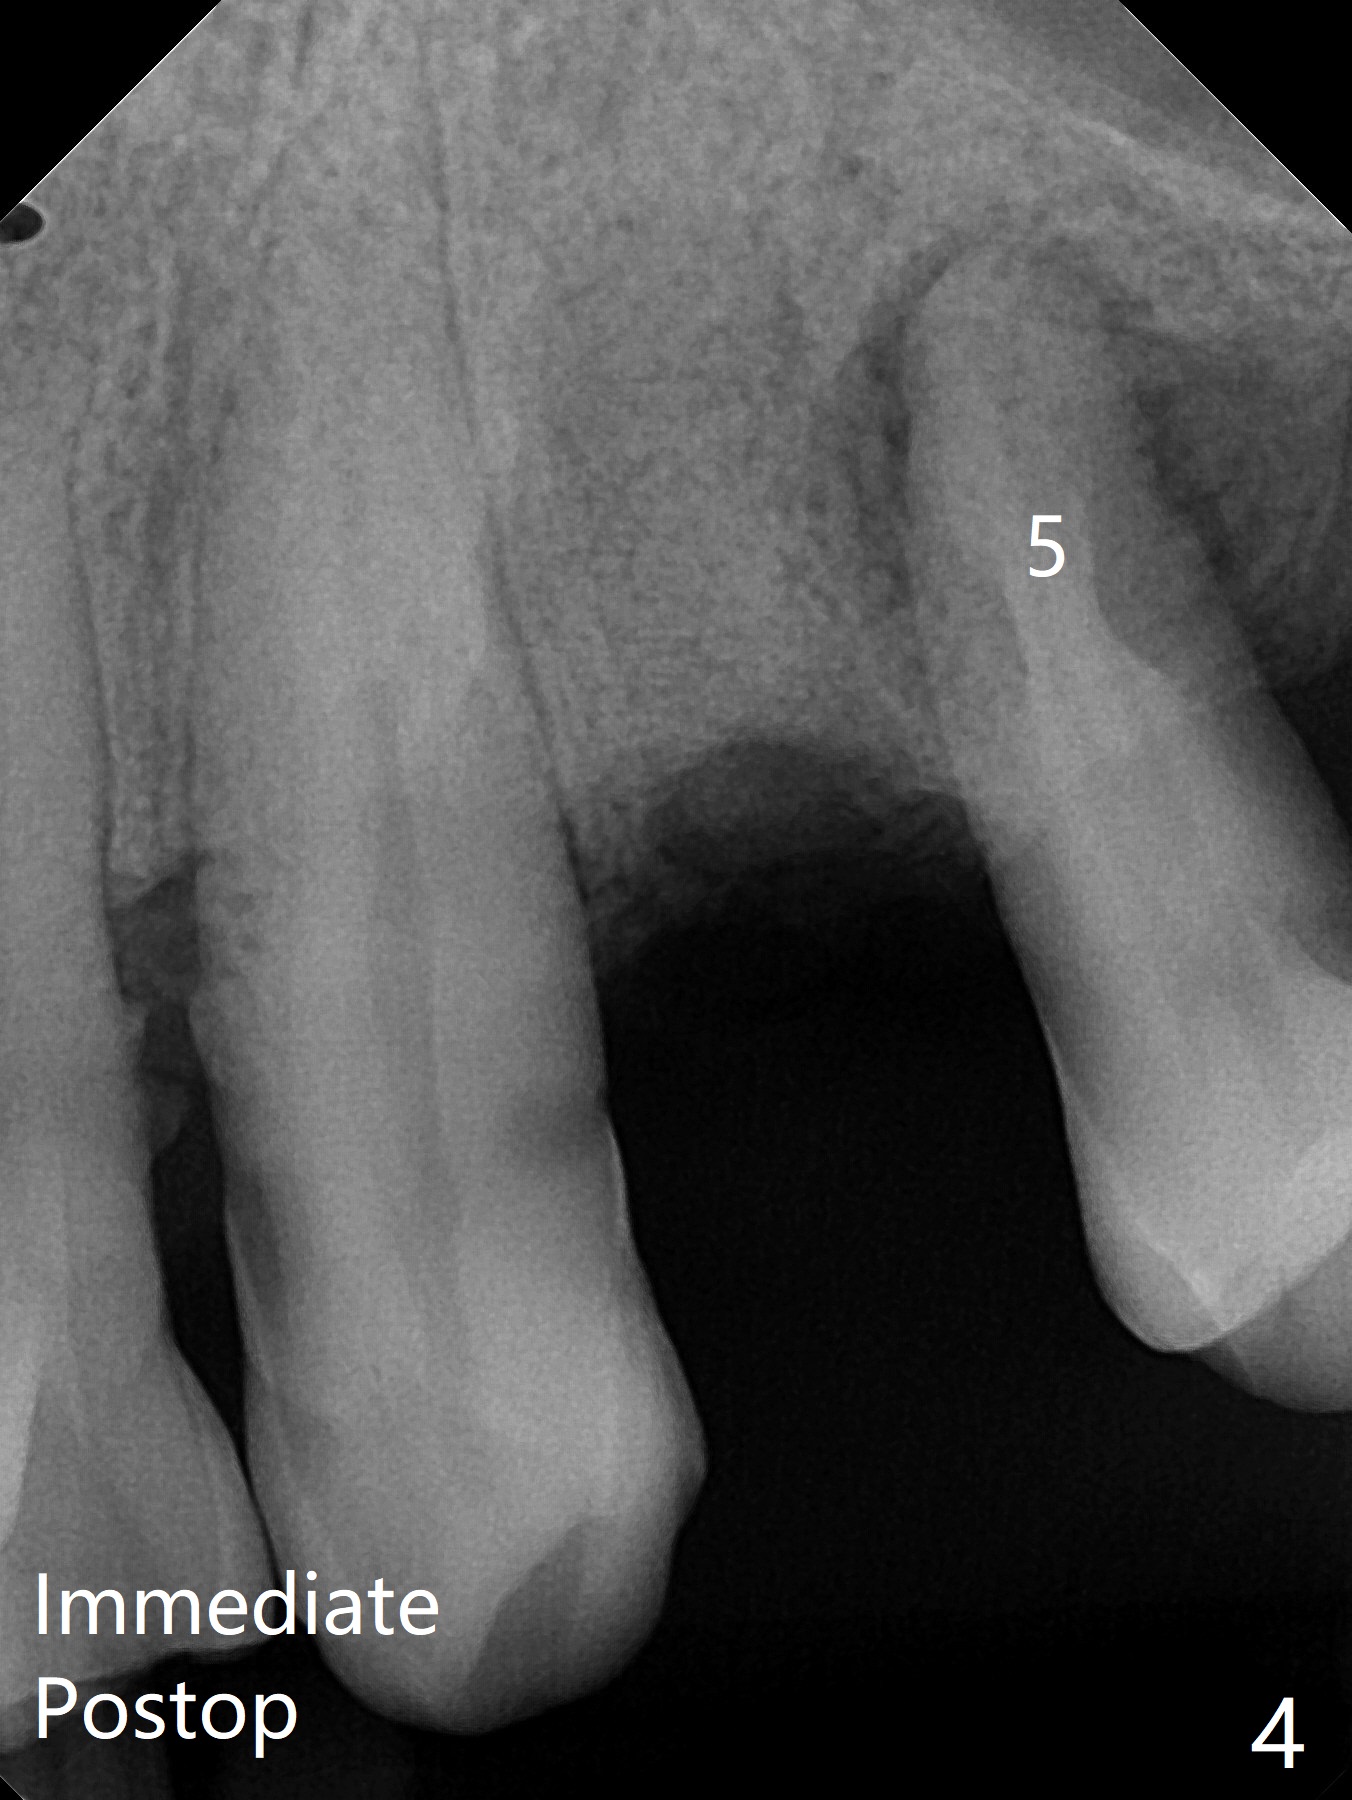

58岁男,吸烟,要求拔除断裂左上4(图一,二),邻牙(5)骨质吸收严重(图一,四),右上4,5拔除后骨质吸收(图一),所以左上4拔除(图三)位点保留(图四:人工骨,图五:GEM Cap)重要,尽管他准备做假牙。

今天手术缺点局麻不足,出血控制不好。明天一早同样病例,左上4拔除,使用两只局麻药(红,绿),准备小纱布塞入牙槽窝止血,植骨前才取出纱布,并且应用骨粉充填器。如果GEM bone matrix没有,使用另外一种人工骨。同样使用GEM Cap覆盖骨粉,利用牙周胶水固定。Return to No Caries Plug Xin Wei, DDS, PhD, MS 1st edition 11/06/2020, last revision 11/06/2020